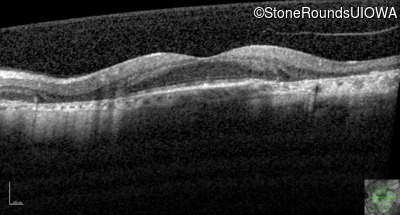

AR Stargardt Disease (IIA)

Age at visit: 51 years

This 51 year old woman first experienced some abnormality in her distance vision when she was 27 years old. She feels that her vision has been stable since that time.

Diagnosis & molecular findings

Disease Gene Allele 1 variant(s) Allele 2 variant(s) Inheritance mode

AR Stargardt Disease ABCA4 Gly1507Arg GGG>AGG IVS42+1 G>A AR